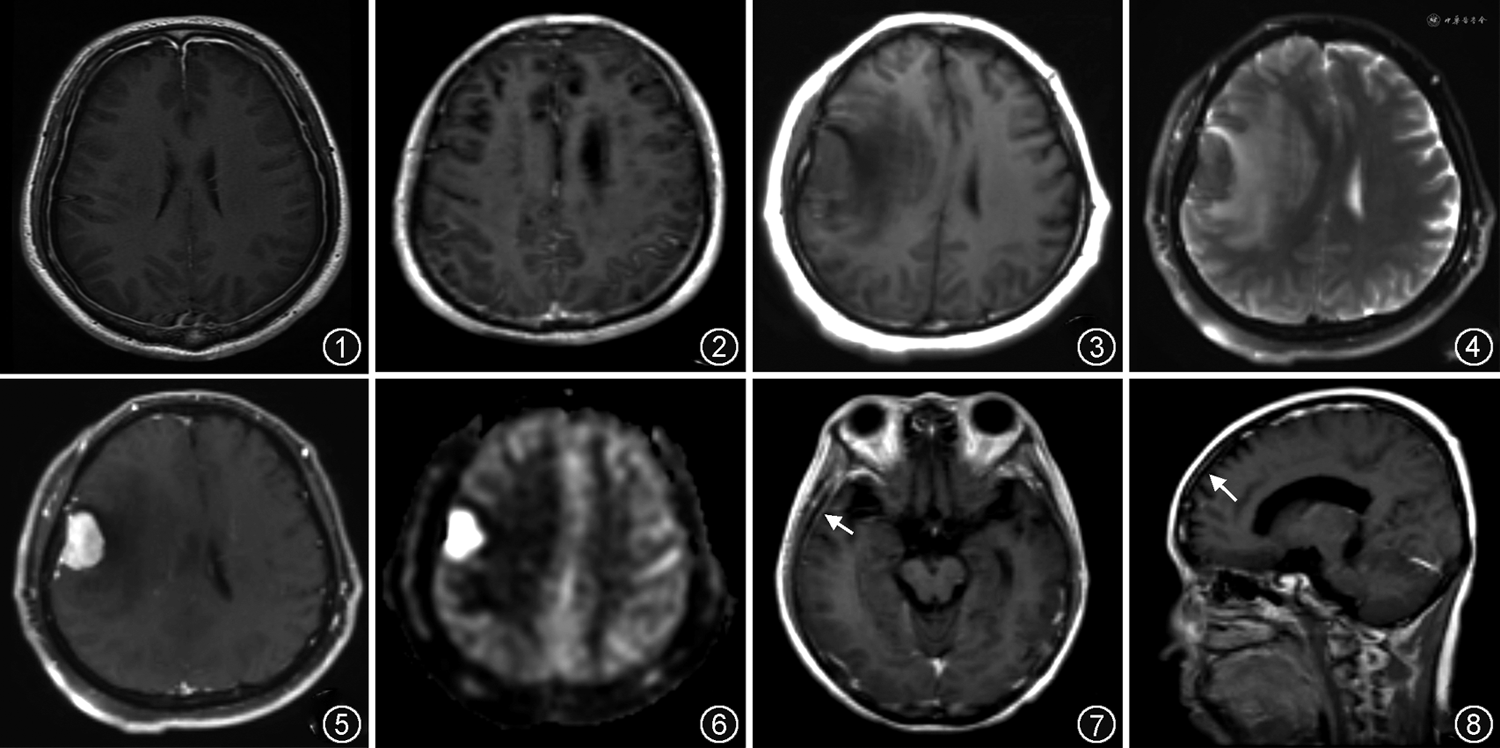

因此脑膜具有两种异常强化模式[2]:(1)硬脑膜强化,为大脑表面连续、增粗的粗线样或结节状强化,可累及大脑镰及小脑幕等结构,不伸入脑沟及脑池(图1);(2)柔脑膜强化,为大脑表面粗线样或结节状强化(图2),特点在于可伸入脑沟及脑池[1]。

脑膜瘤大多为球形或分叶形,边界清晰,以广基底与硬脑膜相连,少数可沿硬脑膜呈浸润性生长,表现为扁平状或盘状。大部分脑膜瘤T1WI呈等或稍低信号,T2WI呈等或稍高信号,增强后一般为均匀强化,约60%病灶伴有硬膜尾征(图3~6),即邻近肿瘤的硬脑膜增厚,增强扫描呈窄带状强化,随着远离肿瘤而逐渐变细呈鼠尾状或线状,但硬膜尾征并非脑膜瘤的特异性表现,也可见于淋巴瘤、胶质瘤等肿瘤[4]。裂隙征也是脑膜瘤的表现之一,指肿瘤与周围脑组织之间存在薄层脑脊液,T2WI呈高信号,代表脑膜瘤无脑实质受累。此外,瘤周水肿、囊变、出血、钙化及瘤内血管征等其他表现也可见于脑膜瘤。PWI被推荐用于区分脑膜瘤、硬脑膜转移瘤及高级别胶质瘤。研究证实肺癌、乳腺癌等肿瘤的硬脑膜转移瘤的rCBF显著低于脑膜瘤。在MRS中,脑膜瘤属于脑外肿瘤,因而不含N-乙酰基天冬氨酸(N-acetyl aspartate,NAA),但胆碱(Choline-containing compounds,Cho)可显著增加,脑膜瘤还可表现为特征性丙氨酸峰增高,而脑转移瘤或高级别胶质瘤中未见显示[4, 5]。

硬脑膜淋巴瘤为脑外肿瘤,多发较单发常见,边界清晰,具有广泛的硬脑膜附着,可伴硬膜尾征,有时硬脑膜淋巴瘤也可表现为块状增厚。硬脑膜淋巴瘤在T1WI上呈等或稍低信号,在T2WI上表现为低信号(图7,8)。由于硬脑膜淋巴瘤为致密细胞性肿瘤,DWI呈均匀较高信号,ADC呈较低信号,表现为明显扩散受限,类似于其他原发性中枢神经系统淋巴瘤[9, 10]。增强后肿瘤明显强化伴硬膜尾征。大多数硬脑膜淋巴瘤病灶可挤压皮质向内移位,并导致邻近的脑实质血管源性水肿,表现为T2WI及FLAIR高信号。其他表现还包括脑实质浸润、骨质破坏及增生等[8],但脑实质坏死、脑积水和软脑膜强化十分少见[9]。硬脑膜淋巴瘤累及颅骨骨质时其表现可类似于脑膜瘤,但多模态MRI可进一步提示鉴别征象。与脑膜瘤相比,硬脑膜淋巴瘤在DWI及ADC中扩散受限更加明显,且有更大范围的溶骨性破坏及邻近血管源性水肿,在PWI中硬脑膜淋巴瘤rCBF更低[11],以及在MRS中出现特征性脂质峰,伴有NAA峰降低,Cho峰增高[10]。